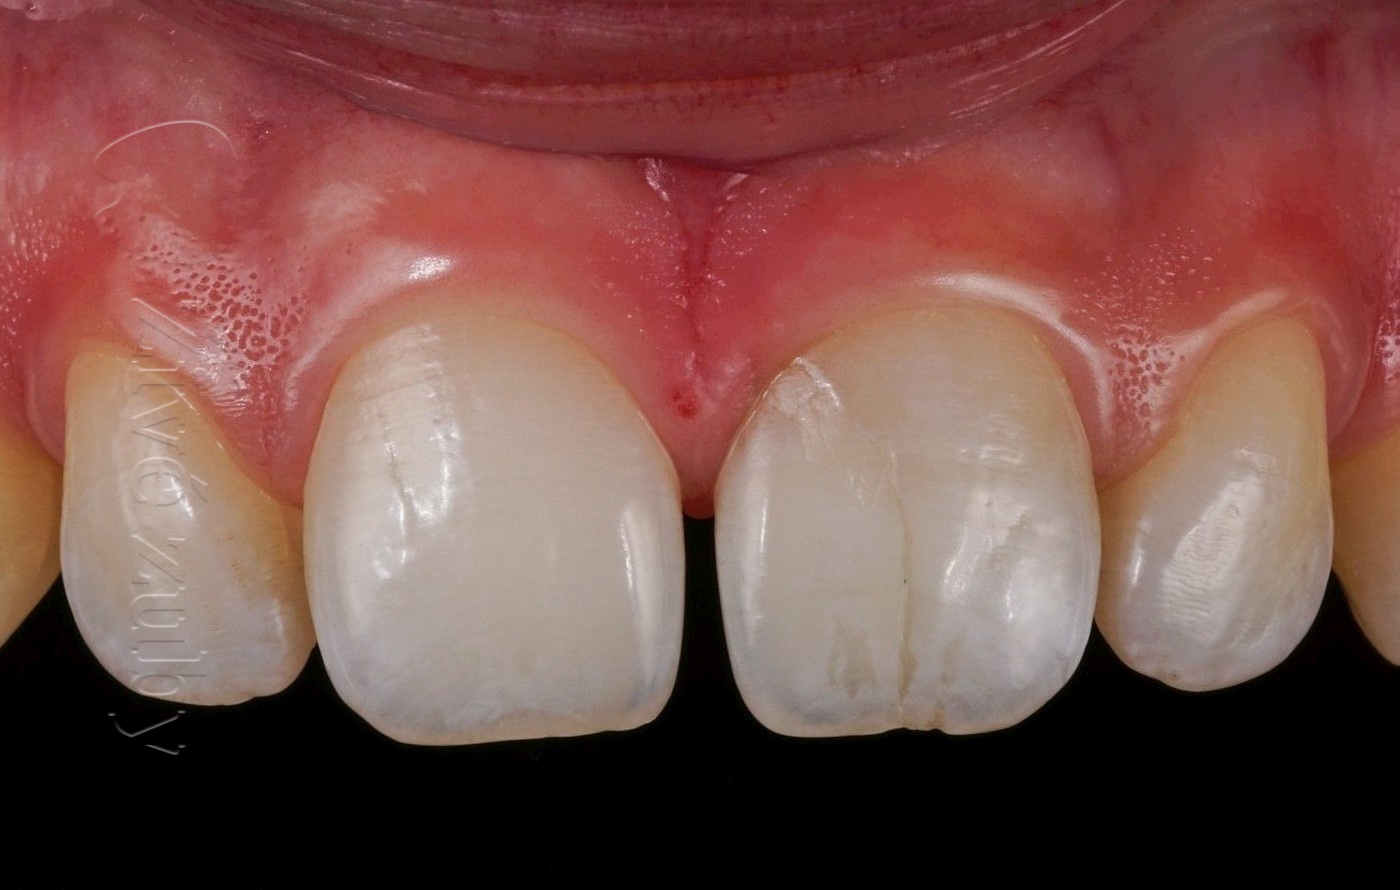

Fraktury zubů

(nekomplikované, komplikované, pulpotomie, … )

Výchozí stav  ——-  Kontrola po 2 letech